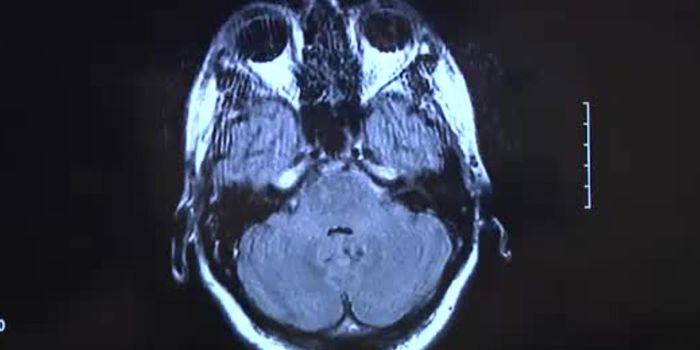

JAN 01, 2018VideosA rare form of brain cancer that strikes mostly children under the age of 10 years old seems centered in a particular ar ...

AUG 31, 2017VideosIn children, brain cancer is the number one cause of cancer-related deaths. Brain tumors are extremely aggressive and of ...